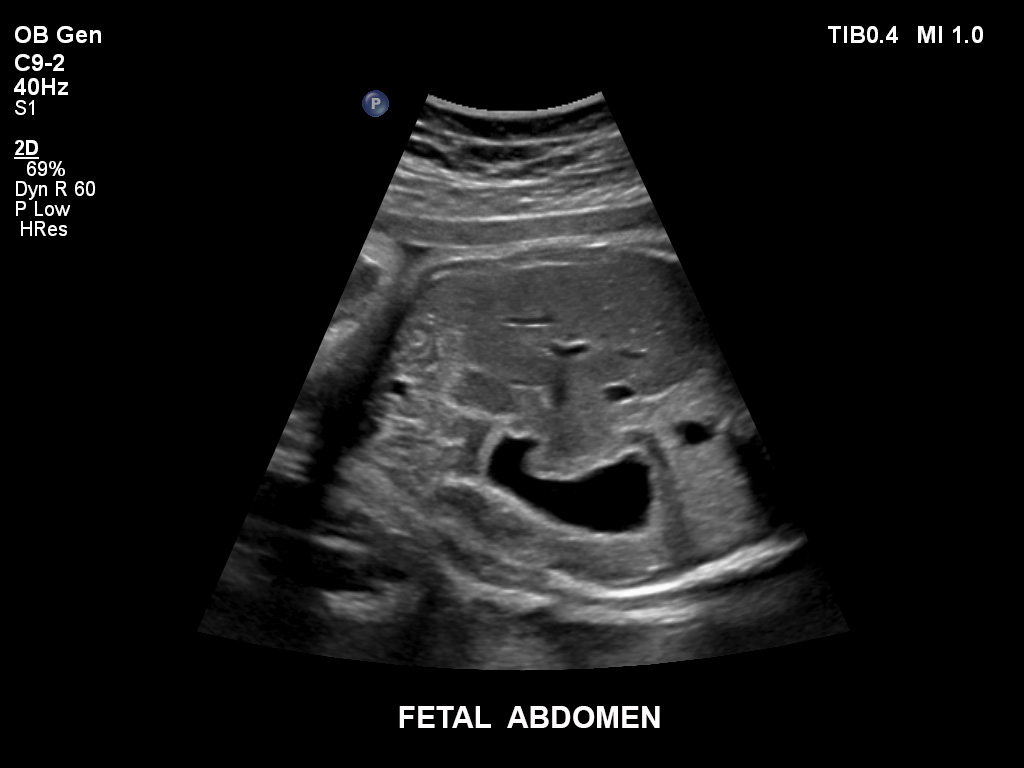

Überzeugende Bildgebung in allen Schwangerschafts­dritteln

Die EPIQ-Produktreihe mit ausgereiften Schallköpfen erfüllt die Anforderungen auch Ihrer anspruchsvollsten gynäkologischen Untersuchungen und während der gesamten Schwangerschaft.

• C9-2 PureWave-Breitband-Convex-Schallkopf für Hochfrequenz-Bildgebung in der Gynäkologie und der Geburtshilfe, insbesondere für die Untersuchung im Hinblick auf mögliche Anomalien im ersten Schwangerschaftstrimester